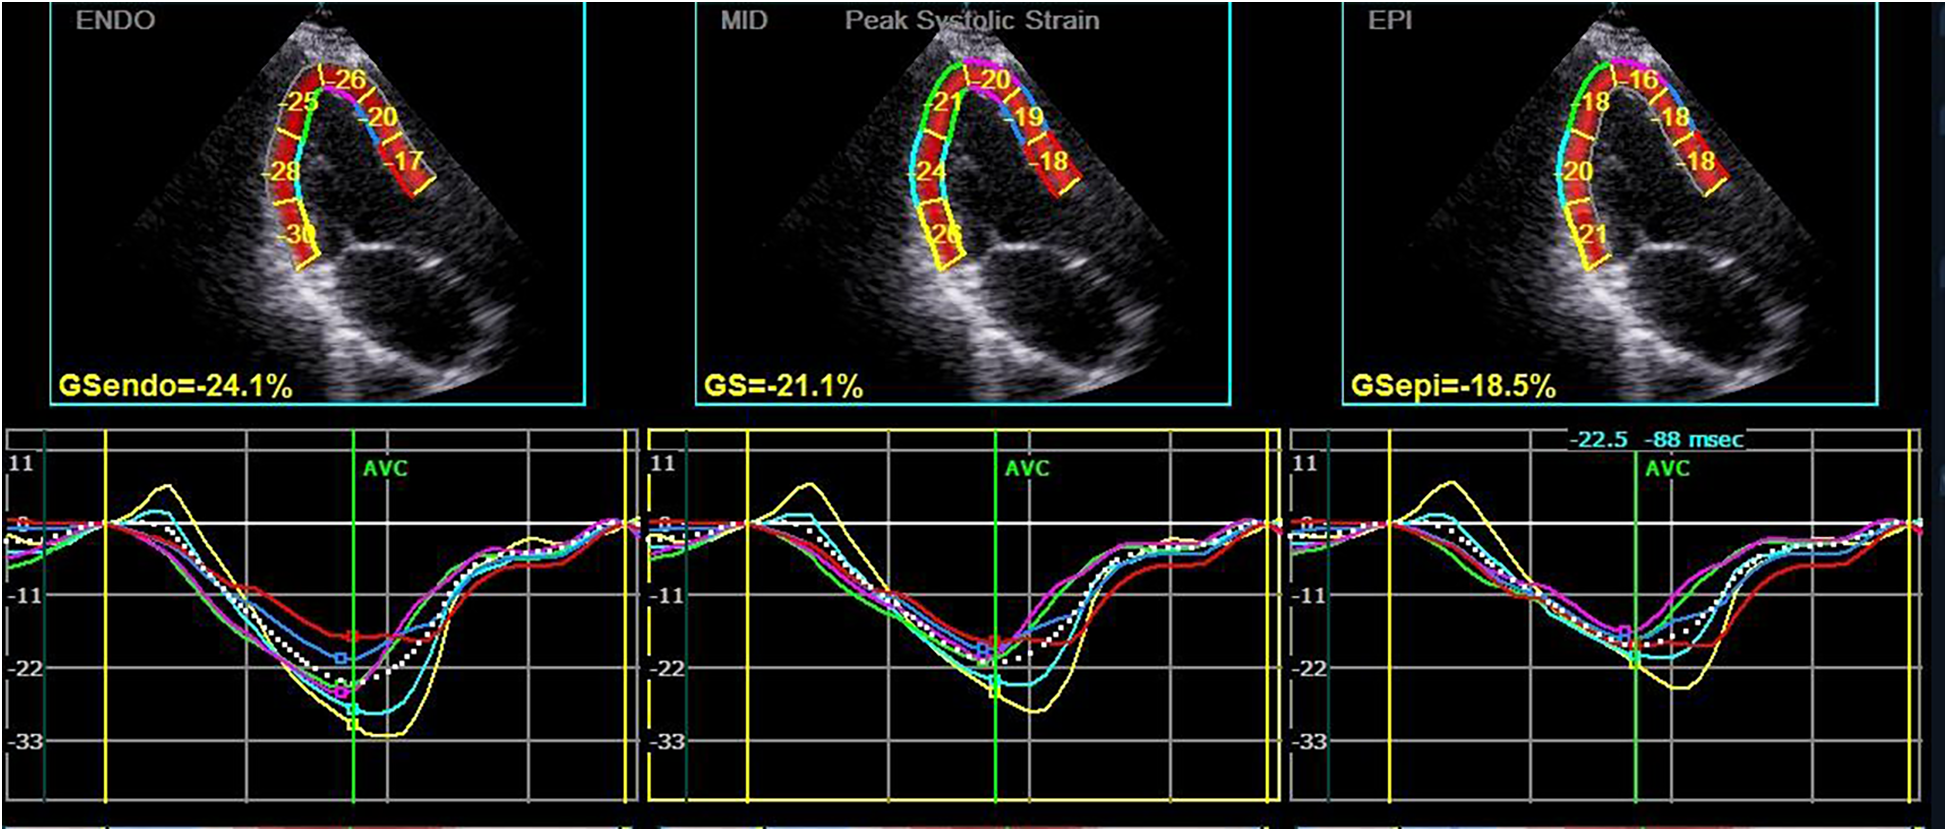

Figure 1

Longitudinal strain and strain curve of the left ventricular myocardium in a hypothyroidism patient. The upper half of the picture depicts the peak systolic longitudinal strain of the endocardium, mid-myocardium, and epicardium (PLS-endo, PLS-mid, and PLS-epi) values of each segment in apical left ventricular long-axis view, and the lower half shows the strain curve corresponding to each segment.

Subsequently, the stored dynamic images were Q-analyzed for 2D strain using the offline EchoPAC113 software. The endocardium of the dynamic images from six views (short-axis and long-axis of the left ventricular) was manually traced. After that, the system automatically segmented the left ventricular wall into inner, middle, and outer myocardial layers, and speckle-tracking analysis was carried out on each layer. Manual adjustment of the region of interest was permitted to ensure optimal tracking quality. The system divided each LV base segment, middle segment, and apical segment into six walls (anterior septum, anterior wall, lateral wall, posterior wall, inferior wall, and posterior septum), resulting in a total of 18 segments (1). Peak longitudinal strain (PLS), peak circumferential strain (PCS), global longitudinal strain (GLS), global circumferential strain (GCS), and the corresponding strain curves for each cardiac cycle were automatically generated (Figures 1, 2), and the relevant bull's-eye figure diagrams were displayed.